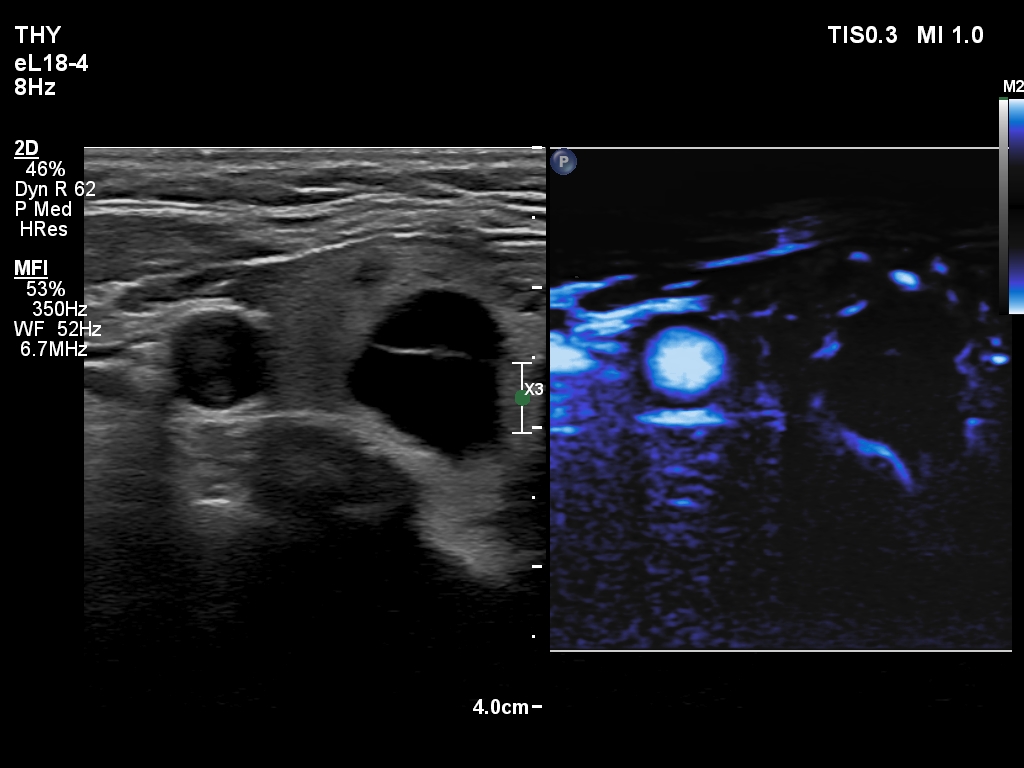

Ultrasonography. The thyroid was echonormal and had multiple nodules. There were cystic areas, an almost completely cystic nodule, and a dominantly solid nodule in the right lobe. The left lobe had three lesions. The upper solid lesion was the one we treated 16 years ago. The middle lesion was a dominantly solid while the lower one seemed to be a pure cyst. The dimensions of the nodule which has been treated with sclerotherapy were 10x11x13 mm (width, depth and length, respectively). There was a large cystic nodule in the upper pole of the left lobe. The lesion showed relatively large hyperechogenic granules. There were multiple enlarged lymph nodes lateral to the left lobe, two of largest were cystic.